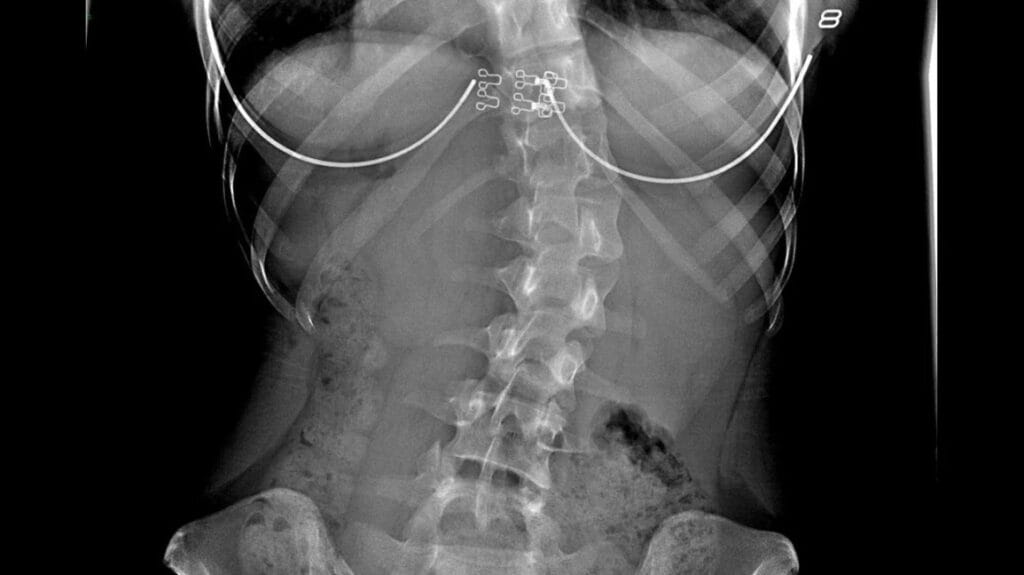

Doktor akan memantau tahap lengkungan melalui X-ray, biasanya setiap 6 hingga 12 bulan. Ini penting bagi memastikan lengkungan tidak bertambah teruk, terutamanya dalam kalangan remaja yang masih membesar atau wanita yang melalui fasa perubahan hormon seperti menopaus.